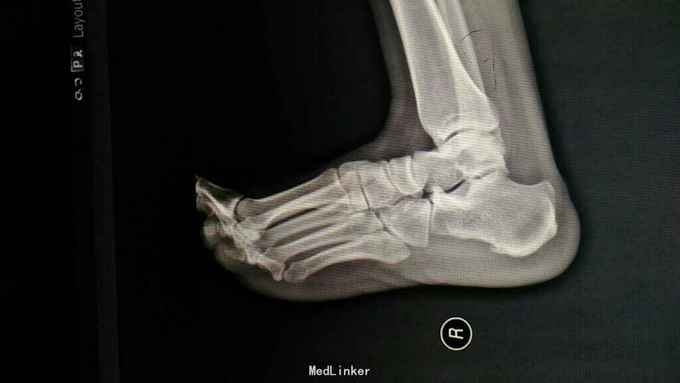

右跟部疼痛2年,加重11月 2年前患者无明显诱因出现右跟部疼痛不适,疼痛活动后加重,休息后突发活动加重,休息后缓解。无肿胀,无局部红肿,无其他关节疼痛,患者于当地医院就诊,行对症用药治疗,疼痛缓解。11月前疼痛再次加重,对症及小针刀等治疗,疼痛不缓解,为进一步治疗入院。

查体:跛行,右跟部外观正常,局部无红肿,跟骨跖筋膜止点处压痛。 X.MRI如下:

诊断:右跟痛症(跟骨骨刺、跖筋膜炎) 治疗:关节镜下跟骨骨刺切除、跖筋膜松解、跟骨减压术